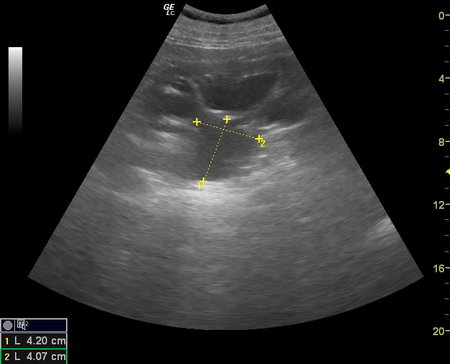

Вот такой случай МКБ с конкрементами в почке и мочеточнике и

роль артефакта мерцания в их уз-диагностике: